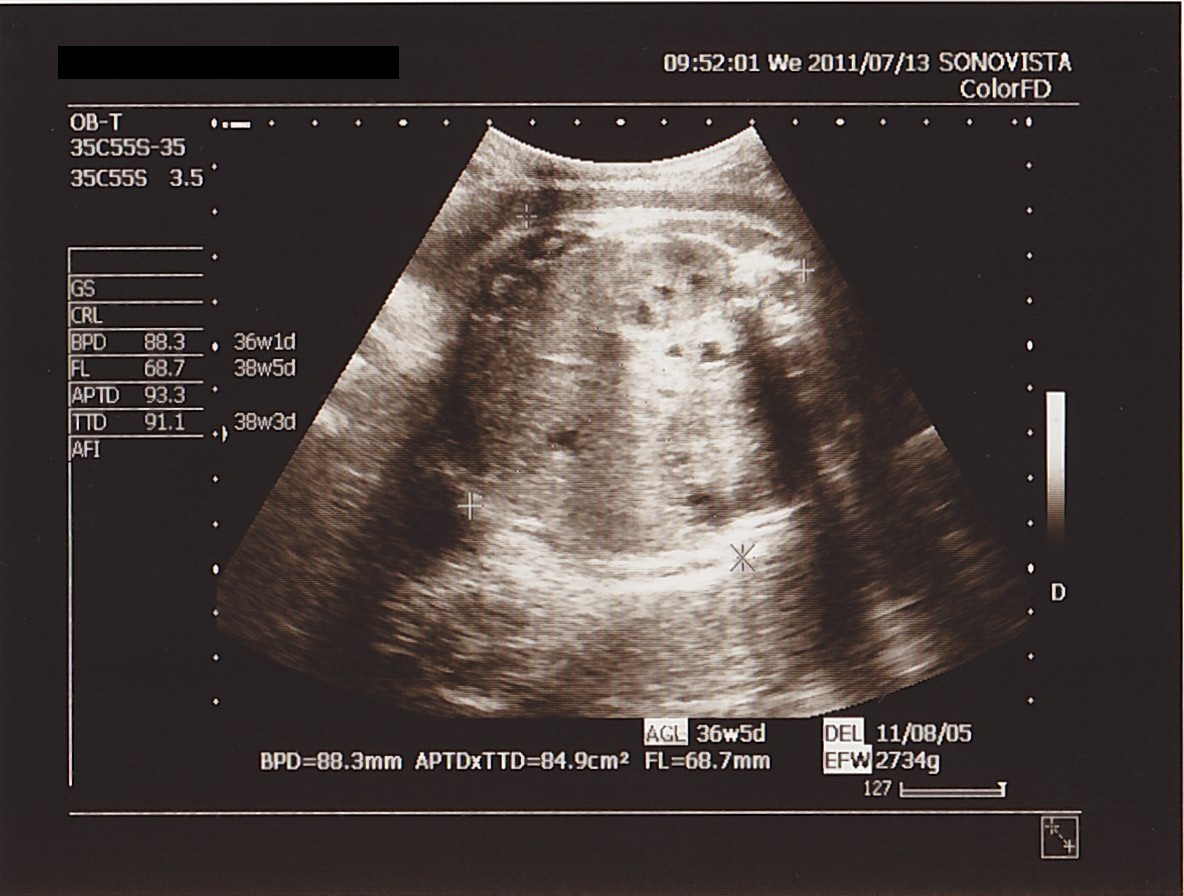

本日の 測定値は

BPD ( 頭の直径 ) : 88.3ミリ

APTD × TTD ( お腹まわり ) : 84.9平方センチメートル

FL ( 太もも骨長 ) : 68.7ミリ ( 再計測時 : 66.6ミリ )

EFW ( 推定体重 ) : 2734グラム ( 再計測時 : 2673グラム )

想定週数 : 36w 5d ( 再計測時 : 36w 3d )

でした。